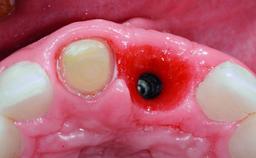

A 36-year-old male patient with a compromised maxillary central incisor was referred by his general dentist for consultation. The patient’s chief complaints were the gradual debonding of a temporary crown on the right central incisor and unsatisfactory esthetics due to an increasing diastema between the right central and lateral incisors. The patient reported a traumatic event some years previously, when a crown had been placed after root-canal treatment. The referring dentist wanted to provide a new crown restoration, but was concerned about the condition of the residual root. Anamnesis was negative for any other dental or periodontal pathology in the remaining dentition. The patient reported taking no medications: He was a smoker (10 to 15 cigs/day) and had realistic esthetic expectations.

Bone Augmentation Horizontal|Simultaneous|Staged

Bone Volume Deficient horizontally, requiring prior grafting